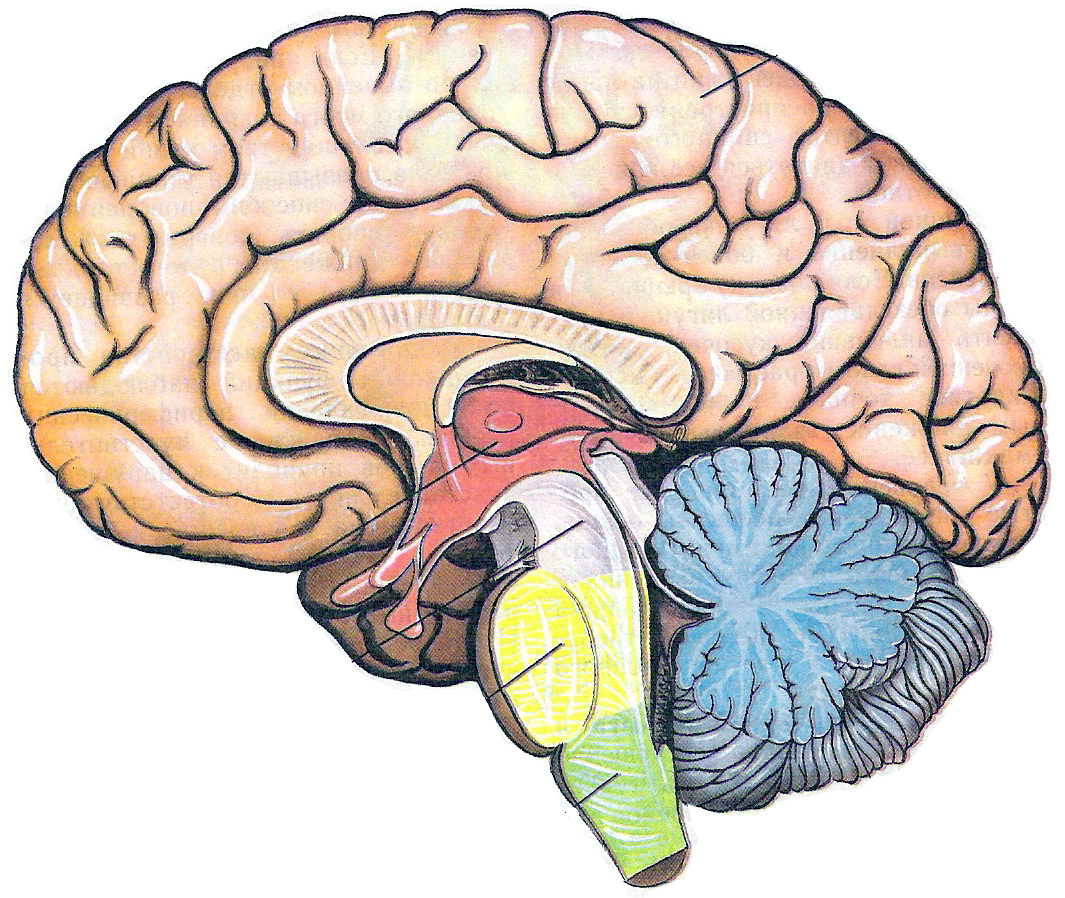

Анатомические снимки верхнелатеральной поверхности головного мозга